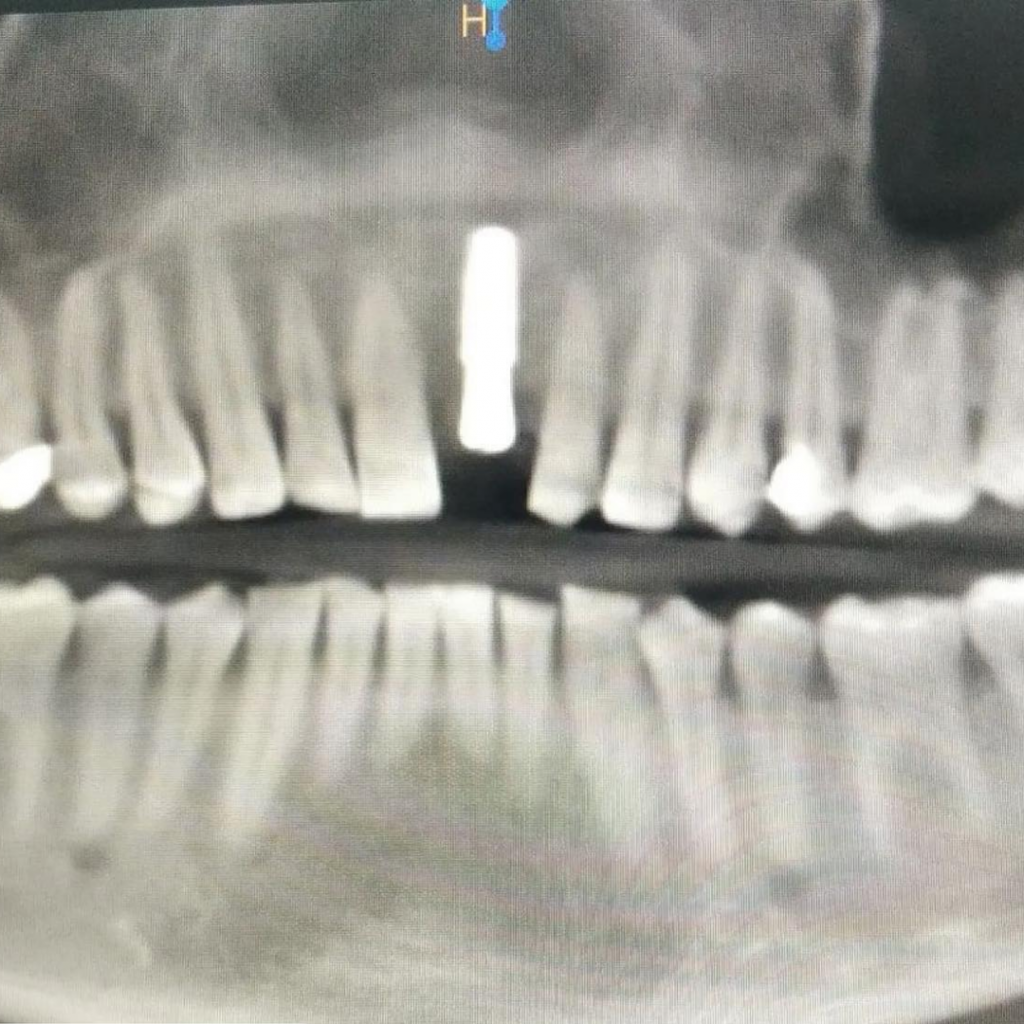

- Лечение: проведена дентальная имплантация AnyRidge в области зуба 2.1 с пластикой десны, а также установлена временная коронка.